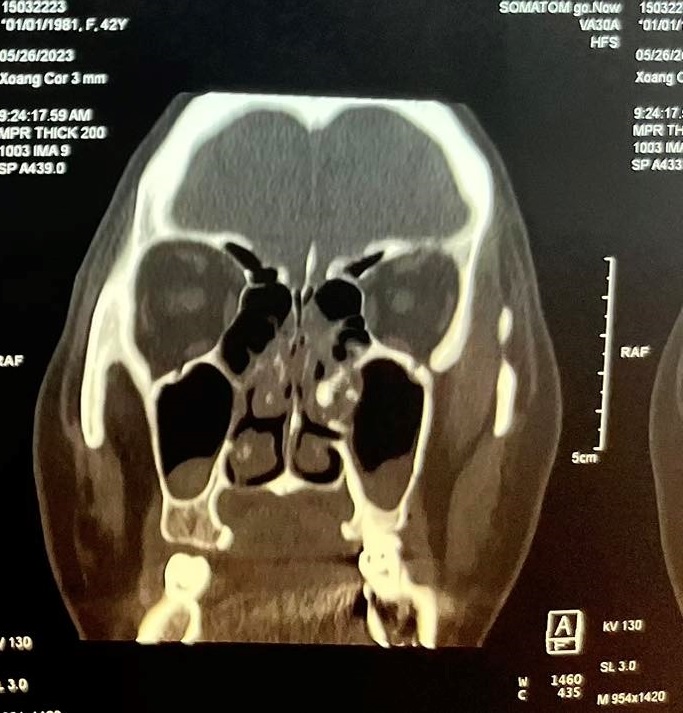

Gần đây bệnh nhân xuất hiện thêm đau nhức vùng mắt trái cùng bên nên đã đến khám tại Bệnh viện Quận 4. Qua nội soi thăm khám và thực hiện chụp CT-Scan phát hiện bệnh nhân có cấu trúc mật độ giống xương dính vào thành trong xoang hàm bên trái, đẩy lệch vách mũi xoang về phía vách ngăn gây hẹp hốc mũi bên trái kèm viêm xoang hàm sàng 2 bên và concha bullosa cuốn mũi giữa bên phải gây tắc nghẽn đường dẫn lưu của xoang hàm bên phải

Hình ảnh CT scans mũi xoang Đánh giá ca lâm sàng, Bác sĩ chuyên khoa II Đào Duy Tường – Trưởng khoa Tai Mũi Họng Bệnh viện Quận 4 nhận định : “ Đây là một trường hợp khá hiếm , tiến triển chậm, bệnh bắt đầu âm thầm ,ít triệu chứng cho đến khi các lỗ thông của xoang bị tắc nghẽn gây ra các triệu chứng đau nhức vùng mặt và khi khối u gây chèn ép hốc mũi bên trái gây cho bệnh nhân có cảm giác nghẹt mũi. Trong trường hợp này phẫu thuật tương đối khó khăn do hốc mũi hẹp, khó tiếp cận khối u , cần phải sử dụng những thiết bị và dụng cụ phẫu thuật chuyên biệt”